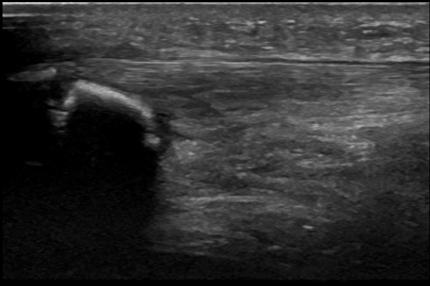

Figure 18 demonstrates a thickened plica visible on ultrasound.

The confirmed cases I’ve seen have mainly been in cyclists.

The patient may describe predictable painful catching or clicking particularly when the extensor mechanism is under load through active flexion.

Consider in cases of what appears to be recalcitrant ‘PFP’.